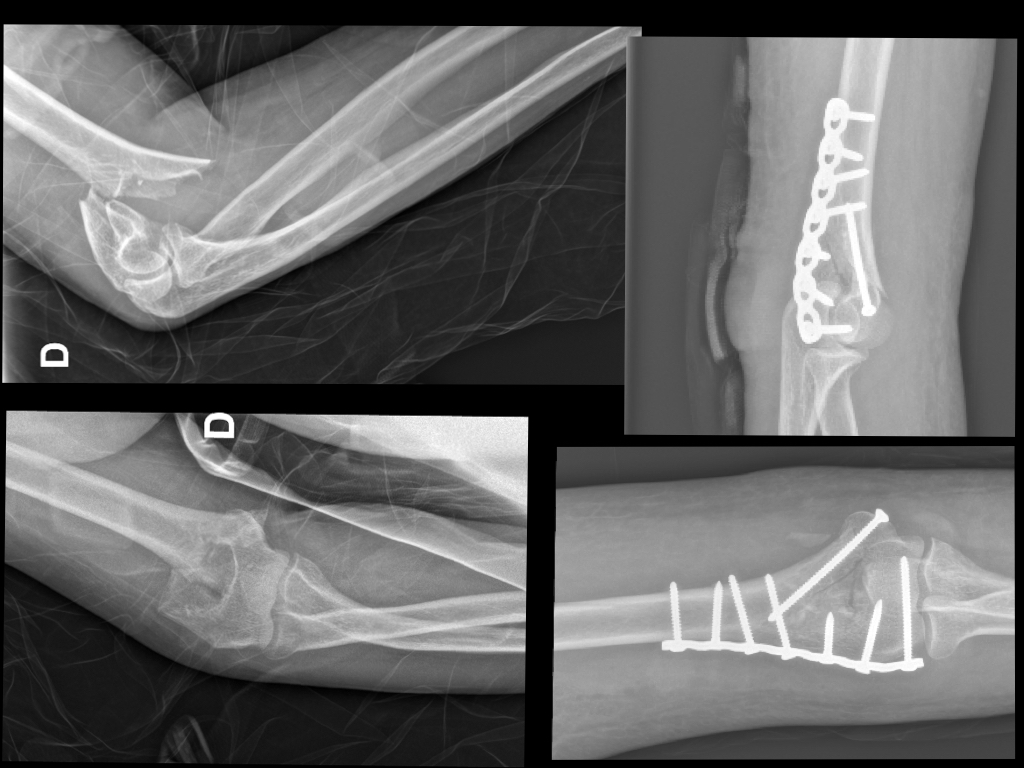

Fractures du COUDE Fractures distales de l humérus Fracture Coude Traitement La fracture du coude désigne le plus souvent la fracture de la parte inférieure de l’humérus, qui est l’os du bras. Le traitement des fractures de l’olécrane repose sur le port d’une attelle, parfois une chirurgie et un traitement par antibiotiques en cas de fracture. Une fracture du coude est une rupture d’un ou plusieurs des os qui constituent l’articulation. Fracture Coude Traitement.